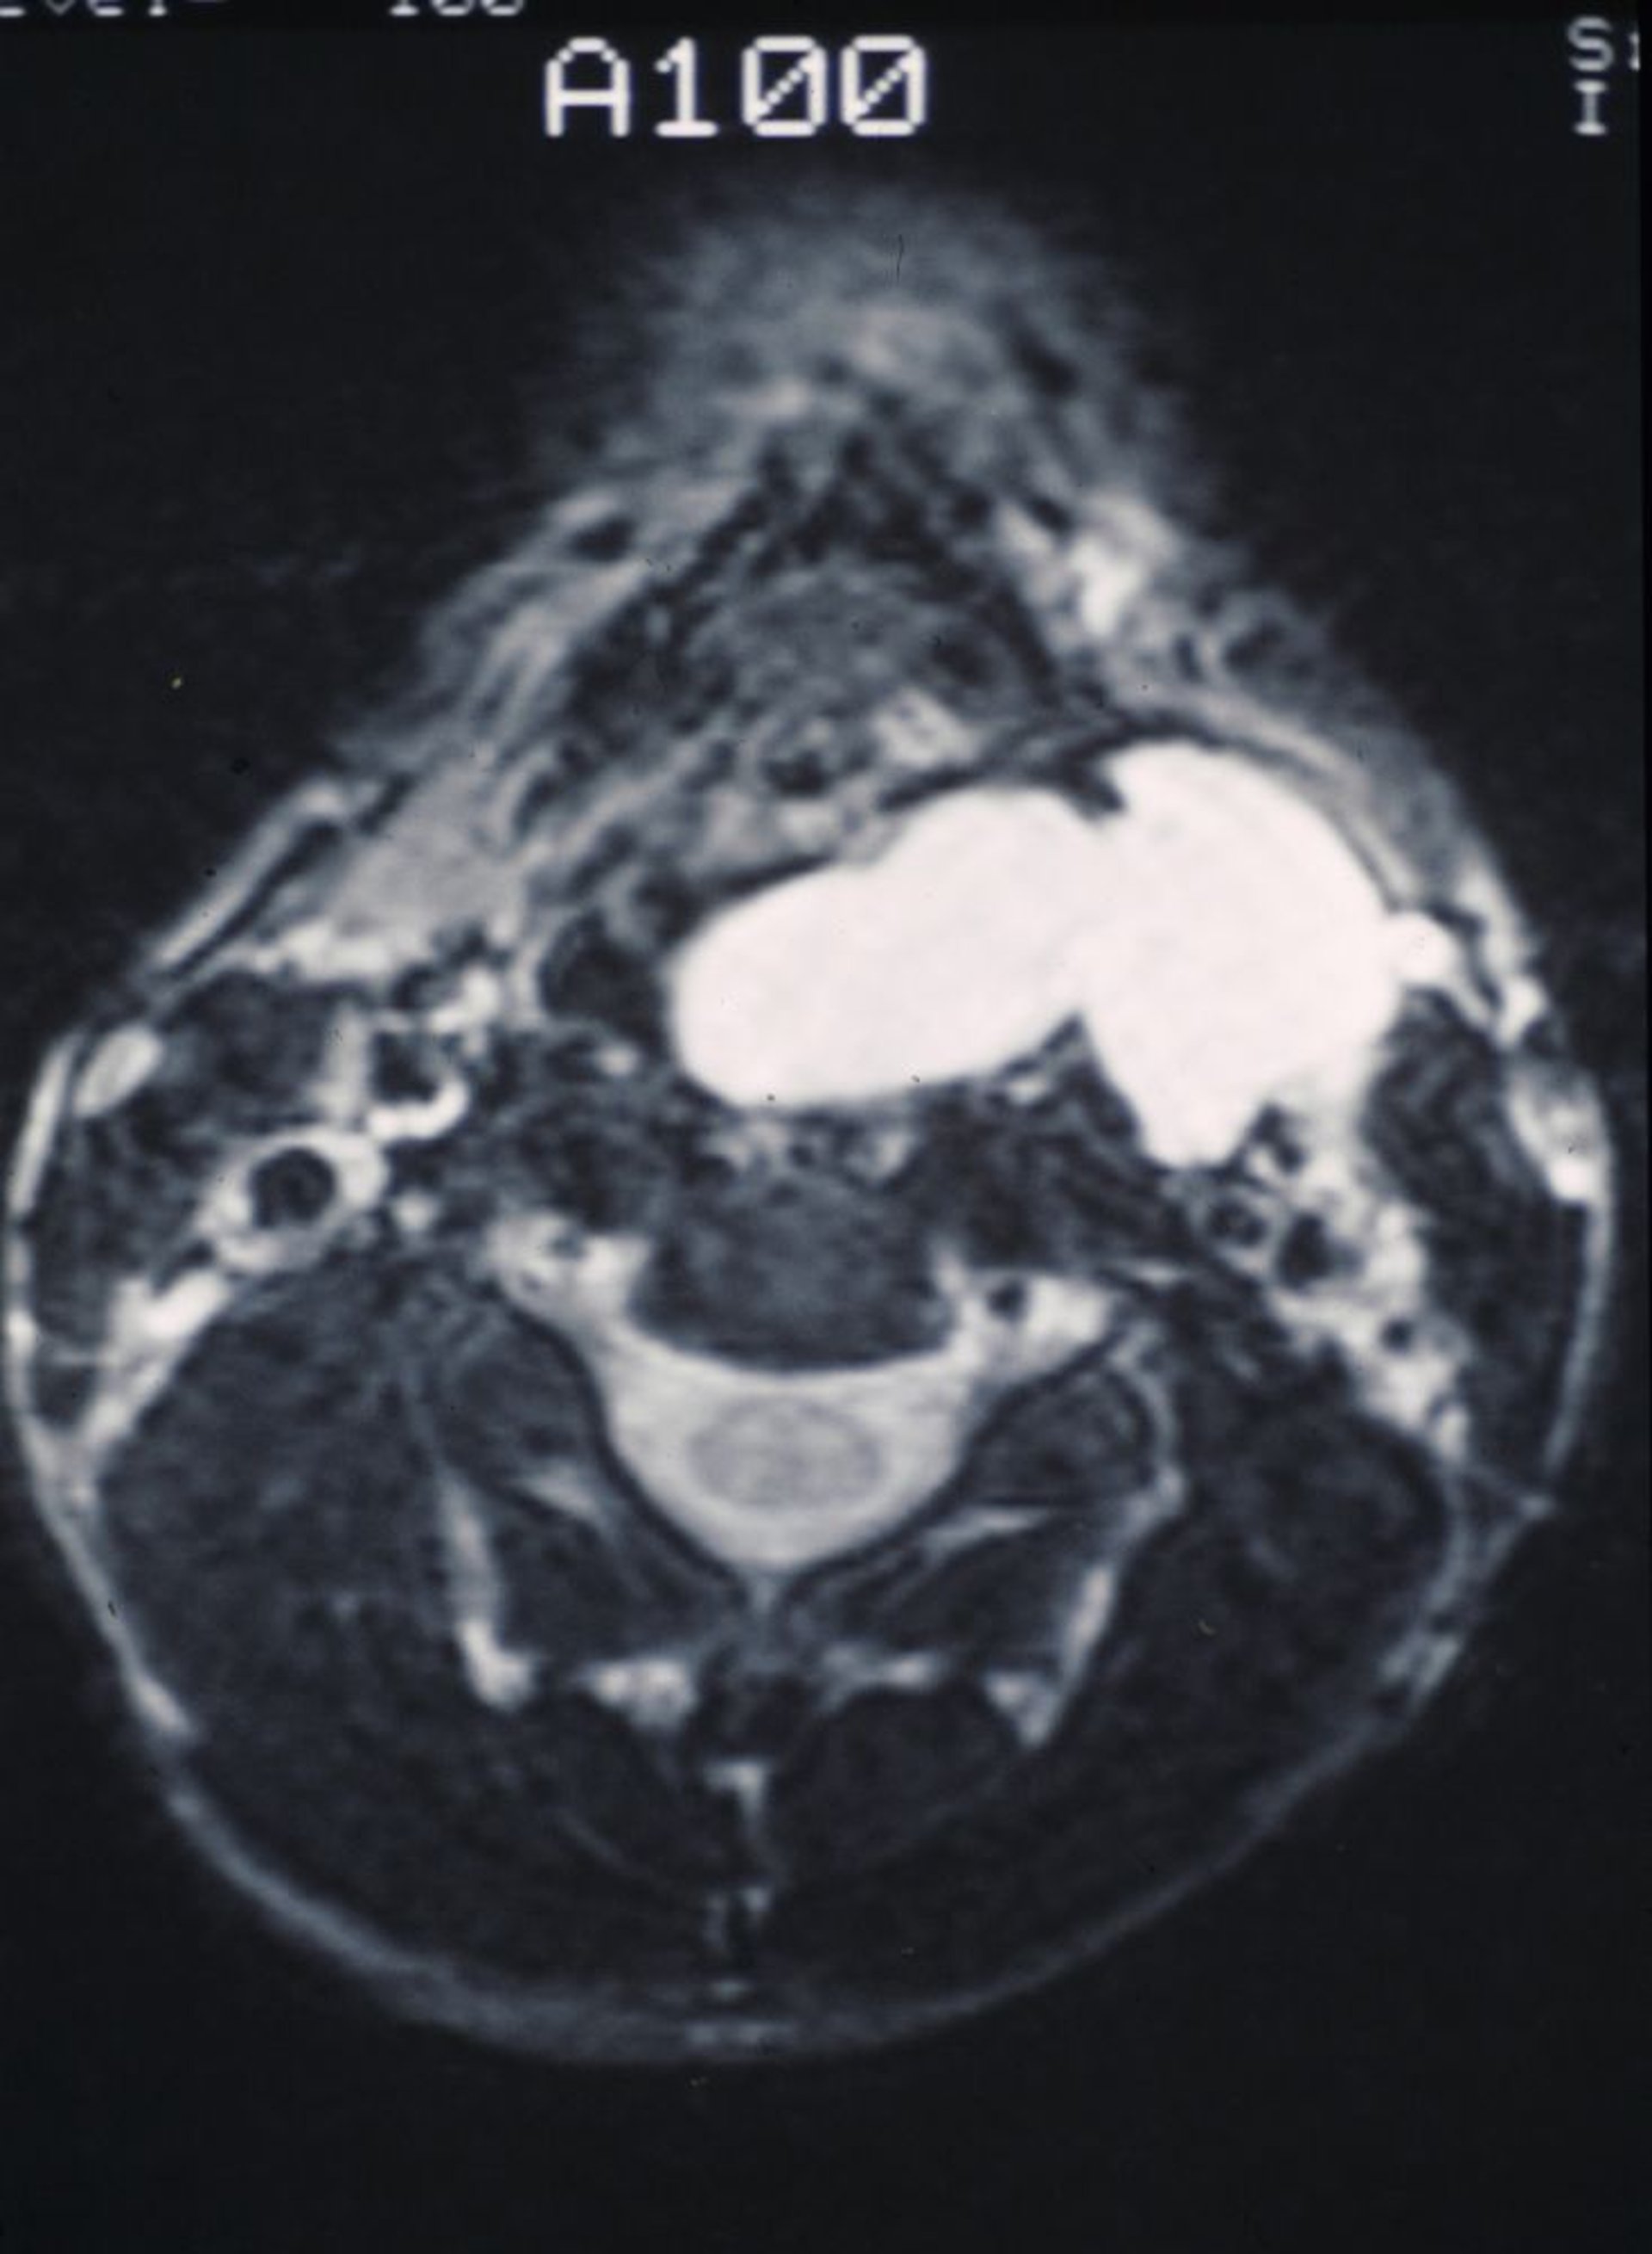

Laryngocèle

Cette IRM montre une laryngocèle lisse remplie de mucus bombée dans la gorge et vers l'extérieur dans le cou.

Image provided by Clarence T. Sasaki, MD.